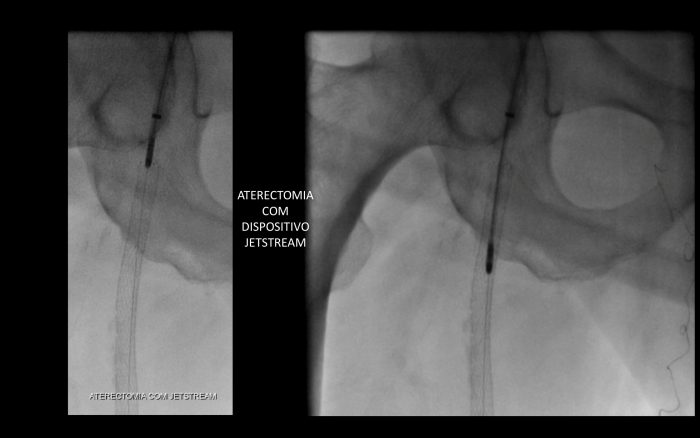

O JETSTREAM é um dispositivo de aterectomia rotacional e aspirativa, desenvolvido pela Boston Scientific, permite recanalizar obstruções arteriais através da redução da carga de placa aterosclerótica, mesmo calcificada ou trombótica, e da hiperplasia miointimal com baixa taxa de embolia distal (1,6%), diminuindo as limitações e complicações da angioplastia tradicional, como dissecção e recolhimento elástico precoce, e sem os efeitos dos elementos sintéticos deixados no vaso como os Stents.

Esse dispositivo de aterectomia pode ser utilizado também em estenoses ou oclusões intra-stent apresentando taxa de recanalização de 91% e sem causar deformidades ou fraturas do stent.